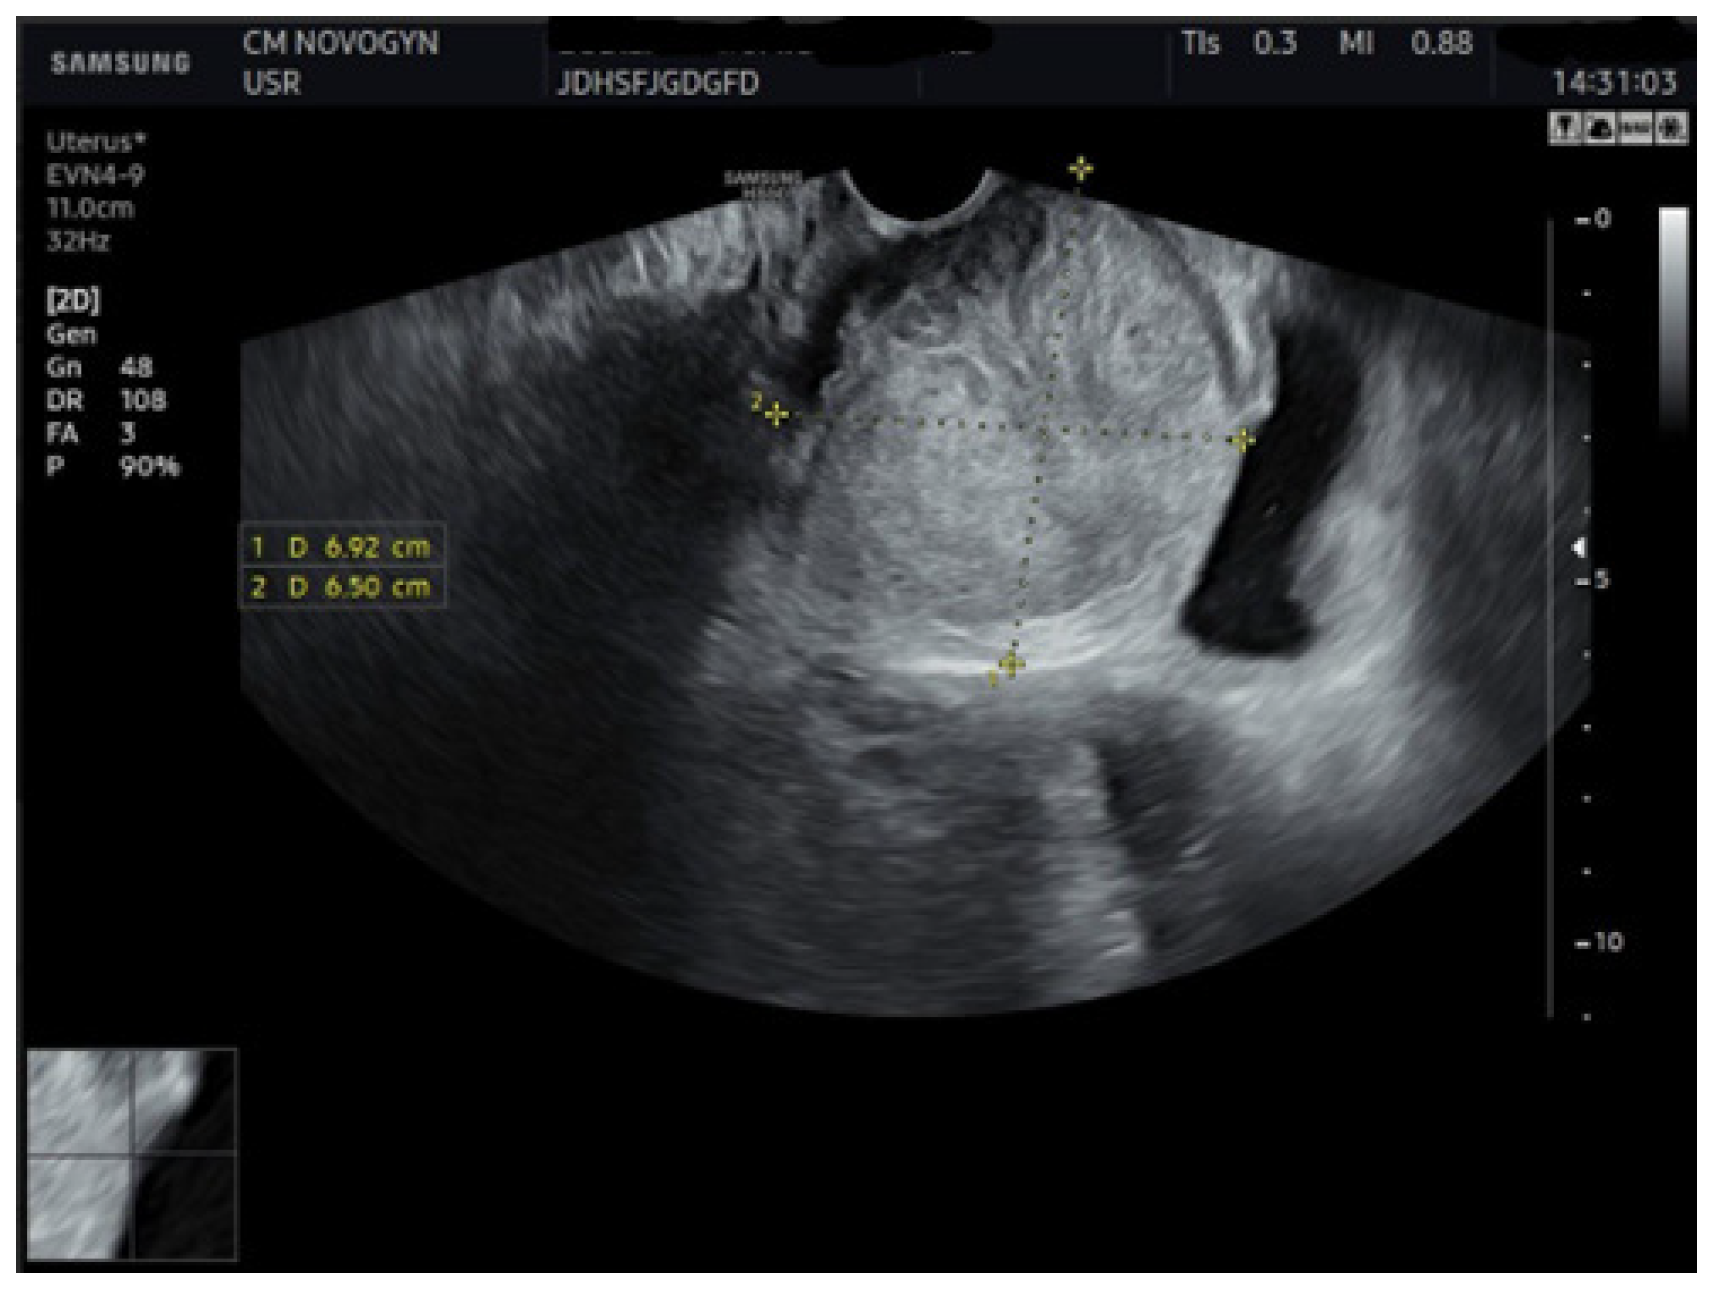

Initial transvaginal ultrasonography revealed a well-circumscribed, solid, predominantly hypoechoic mass measuring (6.9 × 6.5) cm located in the vesicovaginal region (Figure 1). The mass demonstrated homogeneous echotexture with well-defined borders and no internal cystic components. Color Doppler evaluation showed minimal internal vascularity. The uterus measured within normal limits, but demonstrated a fundal contour abnormality suggestive of septate uterus. Both ovaries appeared normal.